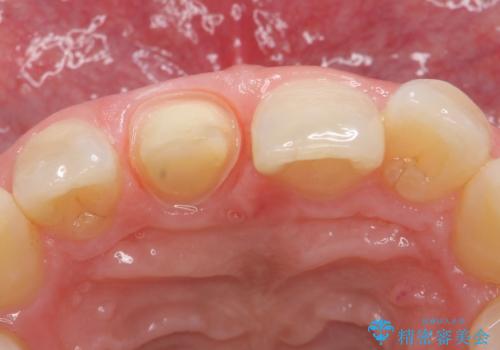

- 他院にて根管治療を行っていたが、痛みが引かないので診て欲しいといらっしゃった方の症例です。

マイクロスコープ下でラバーダムを使用しながら根管治療を行い、痛みが治まった後にオールセラミッククラウンによる補綴を行いました。

- オールセラミッククラウン…¥100,000、仮歯…¥10,000、ファイバーコア…¥20,000費用は治療当時の料金となります

今回用いたオールセラミッククラウンはジルコニアフレームという白い素材の上にセラミックを盛っているため、審美性が非常に高いのが特徴です。

また、ジルコニアは人工ダイヤモンドの材料にも使われているほど高い強度を持っており、そのためオールセラミッククラウンは審美性だけでなく、奥歯やブリッジの補綴も可能とするクラウンです。